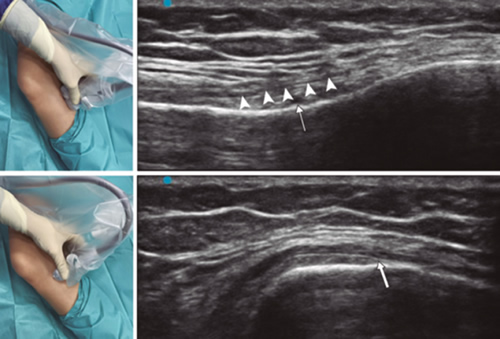

Para lograr una correcta ubicación de las referencias anatómicas por ultrasonido debemos colocar al paciente en posición supina con la rodilla flexionada y una almohada debajo de la fosa poplítea (14,16,19). Después de realizar asepsia/antisepsia de la rodilla, colocación de campos quirúrgicos y de la funda estéril del transductor lineal de alta frecuencia, procedemos a ubicar el NGSM (Figura 3). Colocando la sonda en un plano coronal sobre la cara interna de la rodilla, la deslizamos en sentido craneal hasta visualizar la unión de la metáfisis con la diáfisis femoral y la arteria/nervio geniculado superomedial (ANGSM), usualmente están localizados cerca al periostio del fémur (en caso de no encontrar esta estructura neurovascular, se toma como referencia la unión de la metáfisis y la diáfisis femoral). Después se marca en la piel el punto medio del transductor que corresponde a la ANGSM y se gira el transductor para ubicarlo en el plano transversal o axial para visualizar la ANGSM en eje corto (si no es posible la visualización de esta estructura, confirmar que estamos a un 50 % de la profundidad del fémur). En este corte transversal se avanza la aguja de RFT en plano desde anterior a posterior hacia la ANGSM o hasta una profundidad del 50 % del espesor del fémur. Finalmente se vuelve a girar el transductor 90°, dejándolo en un plano coronal para comprobar que la punta de la aguja está cerca de la ANGSM o de la unión de la metáfisis y la diáfisis femoral (14,16,19).

Fig. 3. Sonoanatomía y técnica para realizar el bloqueo del nervio geniculado superomedial (NGSM). El transductor se ubica en el eje largo distal del fémur y una vez que se tenga la posición del NGSM (asteriscos), se gira la sonda 90 grados para obtener una visión en eje corto del fémur (no olvidar mantener la misma profundidad a la que encontramos el NGSM en el eje largo). VM: vasto medial.

Para ubicar al NGIM (Figura 4) colocamos el transductor en un plano coronal sobre la cara interna de la rodilla, lo deslizamos en sentido caudal hasta identificar la unión de diáfisis con la metáfisis tibial y la arteria/nervio geniculado inferomedial (ANGIM), y repetimos los mismos pasos que usamos para el NGSM. En caso de no encontrar la ANGIM, la referencia que se tomará será la profundidad del 50 % del espesor de la tibia (14,16,19).

Fig. 4. Sonoanatomía y técnica para realizar el bloqueo del nervio geniculado inferomedial (NGIM). El transductor se ubica en el eje largo proximal de la tibia e identificamos el paquete vasculonervioso del NGIM (flecha) justo debajo ligamento colateral medial (puntas de flechas). Luego se gira la sonda 90 grados para obtener una visión en eje corto de la tibia (no olvidar mantener la misma profundidad a la que encontramos el NGIM en el eje largo).

Para ubicar el NGSL, el paciente debe estar en posición supina con el miembro inferior en rotación interna, consiguiendo una buena exposición de la cara lateral del muslo. Colocamos el transductor lineal en un plano coronal sobre la cara lateral de la rodilla, lo deslizamos en sentido craneal hasta visualizar la unión de la metáfisis con la diáfisis femoral y la arteria/nervio geniculado superolateral (ANGSL), y repetiremos los mismos pasos que usamos para el NGSM (14,16,19).